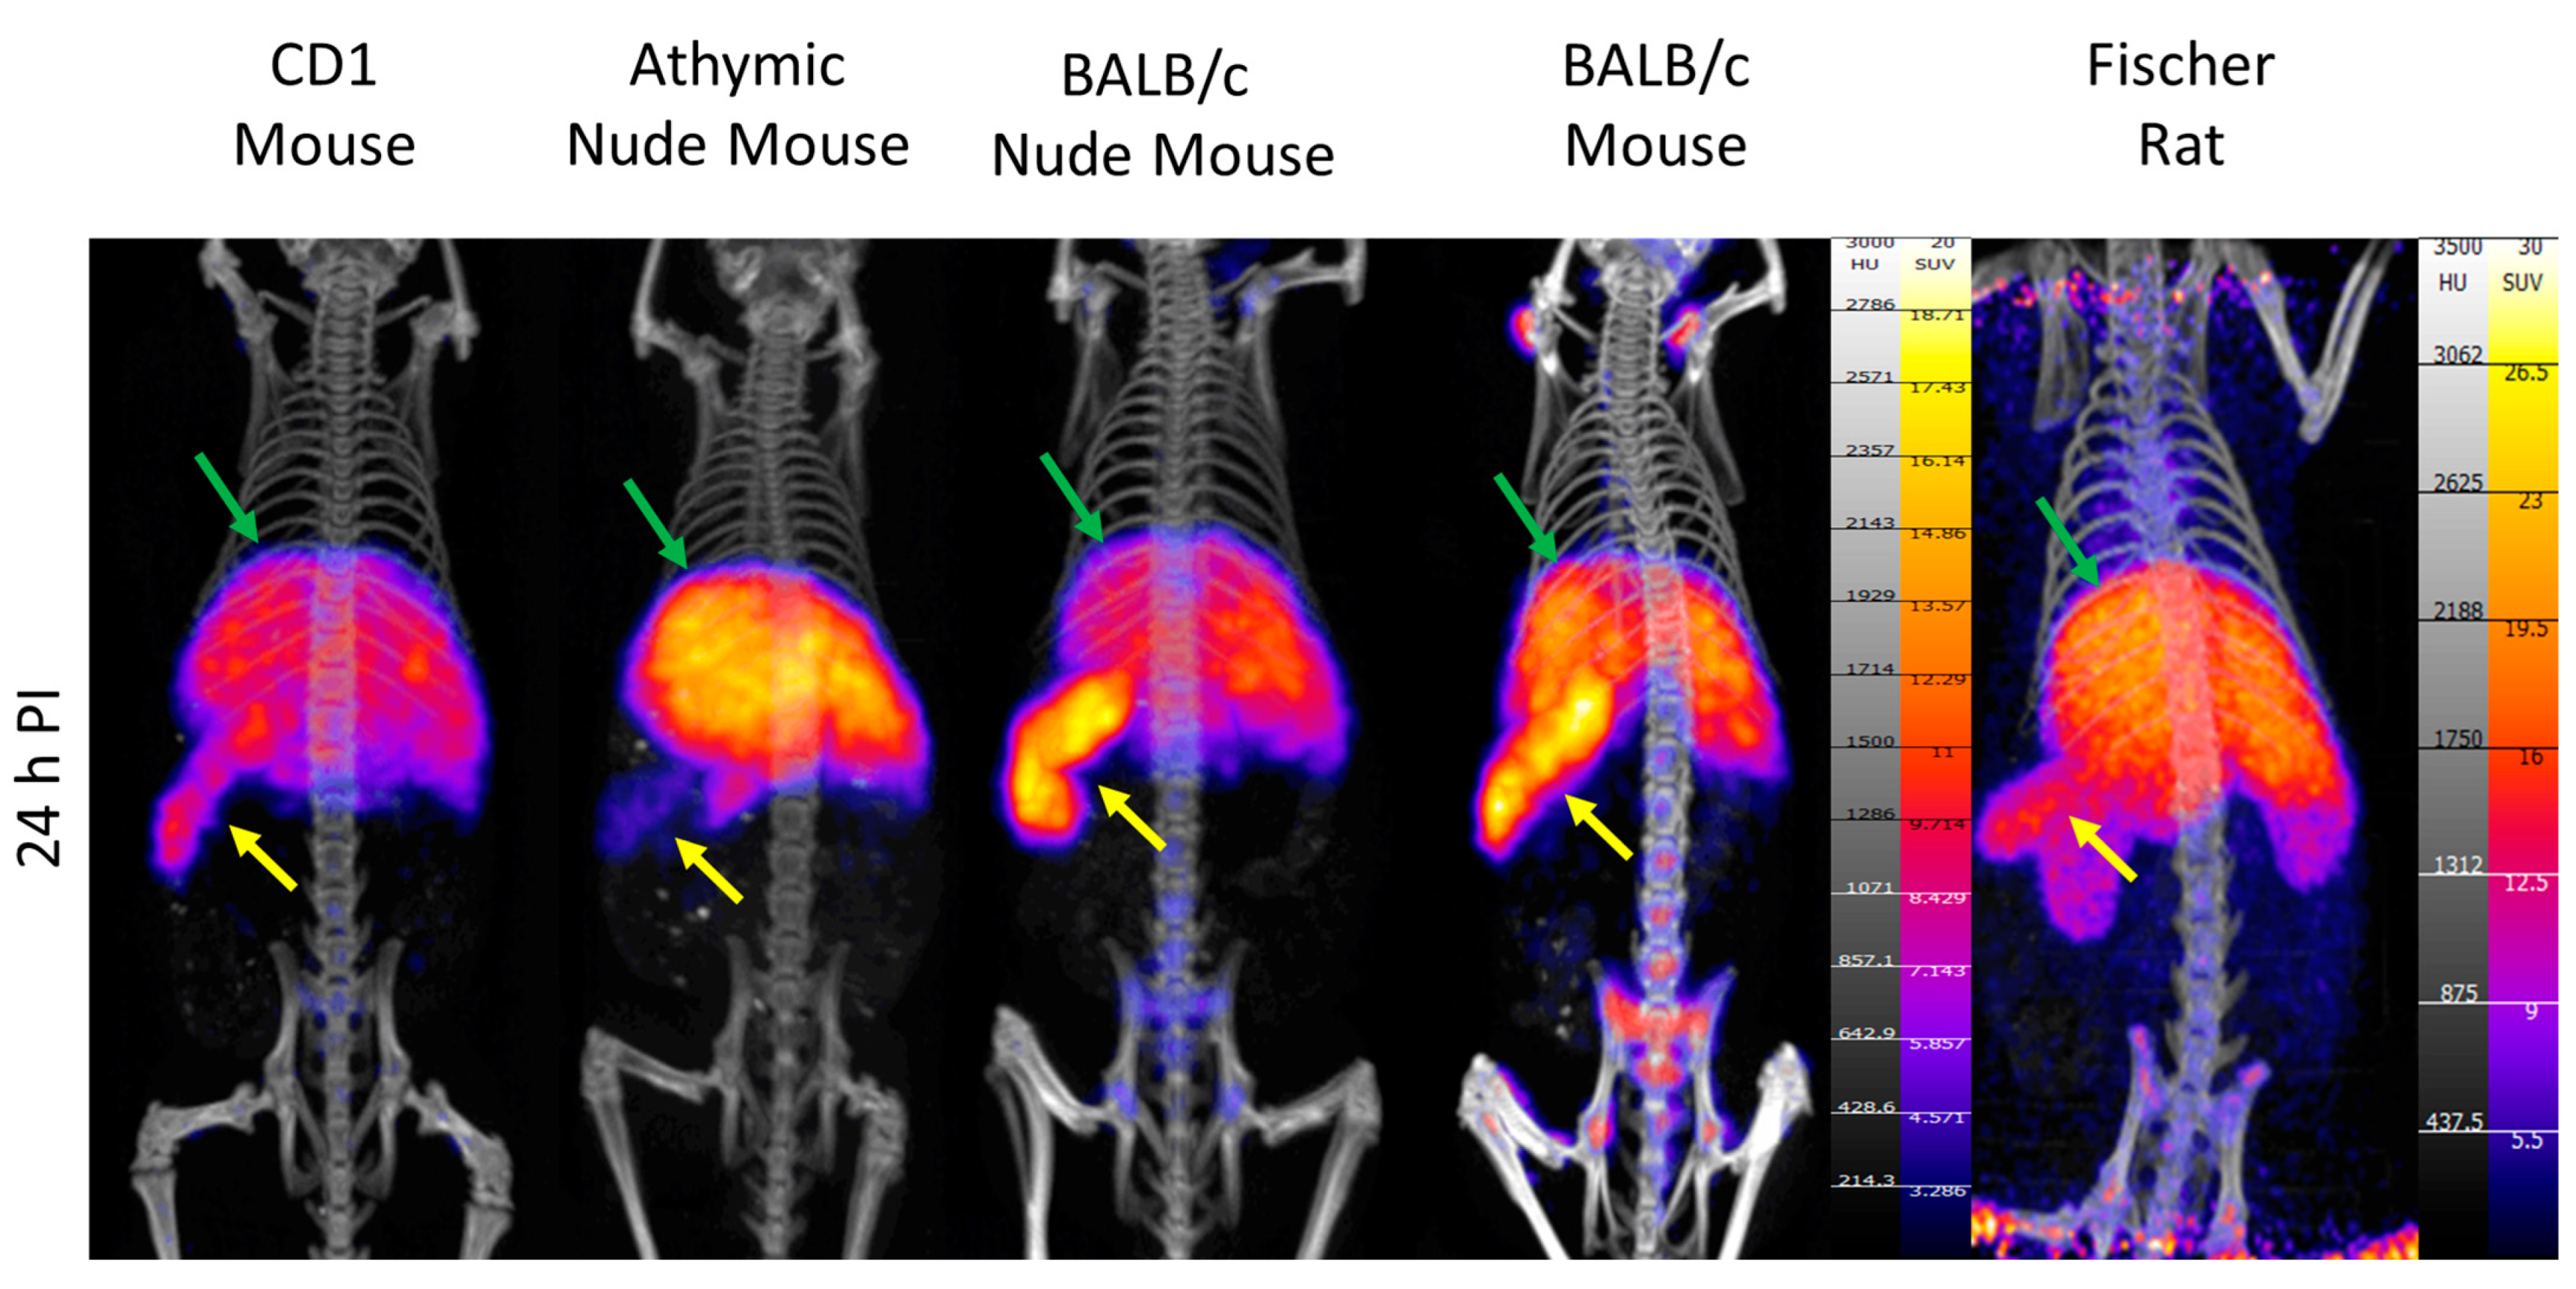

2. Results